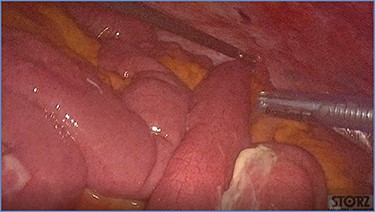

fluid collection in the peritoneal cavity. Subsequent CT confirmed the presence of diffuse fluid collection in the peritoneal cavity (Fig. 1) but no free air, with distention, bundling and thickening of some small bowel in the left quadrant (Fig. 2). The patient was therefore admitted for supporting therapy (intravenous fluids and antibiotics) with the suspicion of cocaine-induced small bowel ischemia. Twelve hours later, signs and symptoms of diffuse peritonitis developed: worsening diffuse abdominal pain with rebound guarding at examination, a significant increase in WBCs count (16.15 × 103/μl) and neutrophilia (88%), lengthening of coagulation times (INR: 1.68; aPTT: 33.0 s) and increase in fibrinogen (430 mg/dl) and D-Dimer (2275 ng/ml). Therefore, urgent surgical exploration of the abdomen through a three-port open laparoscopic approach was performed, confirming the presence of 1200 ml of exudative fluid and fibrin clots (Fig. 3). Several adhesions between greater omentum, abdominal wall and small bowel underwent blunt dissection. Thorough exploration of the small bowel revealed two ischemic segments located at about 50 and 100 cm from the Treitz ligament (Fig. 4). The large bowel appeared normal. The existence of non-visible gastro-duodenal perforations was ruled out with the administration of 500 ml of saline with 20 ml of methylene blue through the nasogastric tube. An iv bolus of sodium heparin, 10 000 IU, was then administered, performing a 30-min peritoneal lavage with 5 l of saline solution at 37°C. After reaspiration of peritoneal lavage, a new complete exploration of the small bowel was performed, showing complete revascularization of the two ischemic small bowel segments (Fig. 5). Two tubular drainage tubes were placed in the left and right colic gutters. Culture examination of peritoneal exudate was positive for multi-sensitive Escherichia coli and Enterococcus, thus confirming bacterial translocation peritonitis. Postoperative therapy included the administration of iv piperacillin–tazobactam and subcutaneous low molecular weight heparin. Postoperative recovery was smooth, with oral feeding on the second postoperative day (POD), drainage removal on POD 3, complete bowel function restored on POD 4 and home discharge on POD 5. At 15- and 30-day-follow-up, the patient showed full recovery, being now followed by a specialized support structure for his drug abuse.

Dilated small bowel loops at laparoscopic exploration: bowel ischemia is evident from the absence of visible vasa recta compared to the adjacent loops (a) 50 cm and (b) 100 cm from the ligament of Treitz.